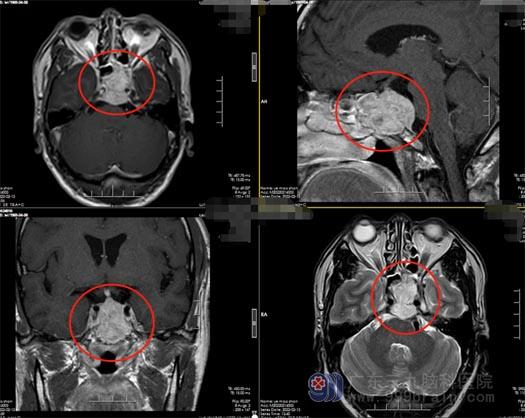

52岁的叶先生,三个月前开始出现视物模糊,起初没有重视,逐渐合并出现视物重影,以左侧眼睛视力下降较明显,到当地医院检查,头部CT发现:鞍区病变。

神经外五科主任王国良教授为叶先生进行了详细的病史了解及影像检查,初步考虑是垂体腺瘤。王主任介绍:垂体瘤是一种导致神经内分泌功能异常的颅内常见的肿瘤,随着肿瘤不断的生长,压迫周围的视神经,引起视力减退、视野缺损等表现,手术切除肿瘤是最佳的治疗方案。